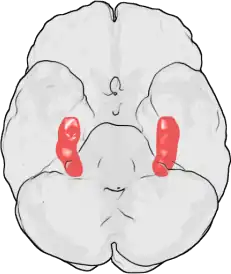

Hipocampo

Hipocampo é uma estrutura localizada nos lobos temporais do cérebro humano, considerada a principal sede da memória e importante componente do sistema límbico. Além disso é relacionado com a navegação espacial.[1]

Seu nome deriva de seu formato curvado apresentado em secções coronais do cérebro, se assemelhando a um cavalo-marinho (Grego: hippos = cavalo, kampos = monstro marinho).[1]